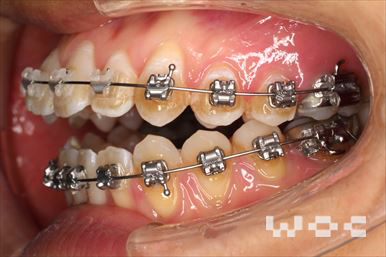

治療中1

治療中2

治療中3

治療中4

治療中5